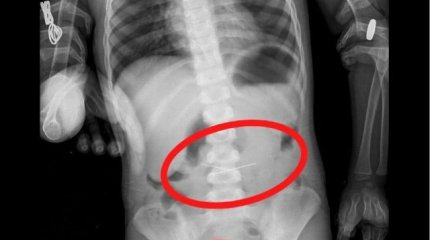

ШҚО-да батарейка жұтып қойған бүлдіршінді дәрігерлер тұмау деп емдеген